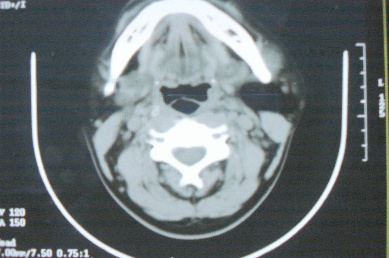

ct10755,男,28岁。发现左侧腮腺区肿块几年,今要求ct检查。左侧腮腺区低密度影,ct值-153hu。

左侧腮腺区囊状低密度影,ct值-153hu,考虑腮腺脂肪瘤。

病灶为一边界清晰脂性区,其内未见实质性组织.支持考虑:左侧腮腺脂肪瘤可能性大.

ct能定性的良性肿瘤不多,对脂肪瘤的诊断是比较有把握的,加大窗宽还可以看到里面有分隔

ct值-153hu,腮腺脂肪瘤。